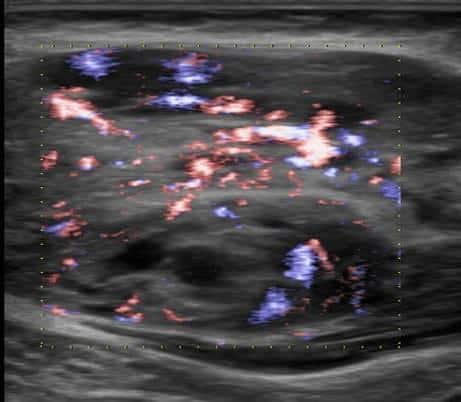

U xơ cơ

» Thông tin: Nữ giới – 3 tháng tuổi.

» Lâm sàng: Sưng vùng đùi.